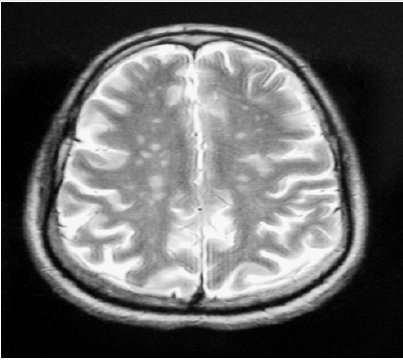

The ophthalmological examination revealed bilateral keratoconjunctivitis with positive Schirmer’s and a breakup time tests. The labial minor salivary gland biopsy showed focal lymphocytic sialoadenitis with a focus score at 2. The immunological tests objectified positive anti-nuclear, anti-SSA and anti-SSB antibodies. Brain magnetic resonance imaging (MRI) showed multiple lesions of the periventricular deep white matter and centrum ovale, in T2 and FLAIR hypersignal, T1 hyposignal, and enhancing after Gadolinium injection (Figure 1). Lumbar puncture and cerebrospinal fluid analysis were without abnormalities. Thus, the diagnosis of pSS with central neurological damage was retained according to the European classification criteria for Sjögren’s syndrome without clinical signs or immunological markers of other connective tissue disease. The anti-depressant treatment was stopped, and the patient was treated with three boli of methylprednisolone (1g/day) followed by oral corticosteroid therapy at a dose of 1mg/kg/day for four weeks. The evolution was favorable with disappearance of functional complaints and disappearance of depressive symptoms. The control brain MRI at six months of treatment was normal. Currently, and two years later, the patient is still stable without any psychiatric symptoms.

Figure 1: Axial T1-weighted brain MRI with injection: multiple hypersignals of deep periventricular white matter enhancing after Gadolinium.